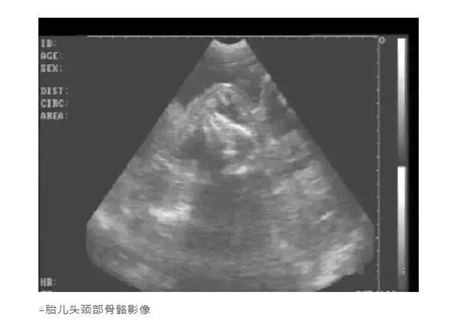

用B超检查母猪妊娠情况,怎样根据显示的图像辨别妊娠状态呢?详细的图文教学分享给大家!